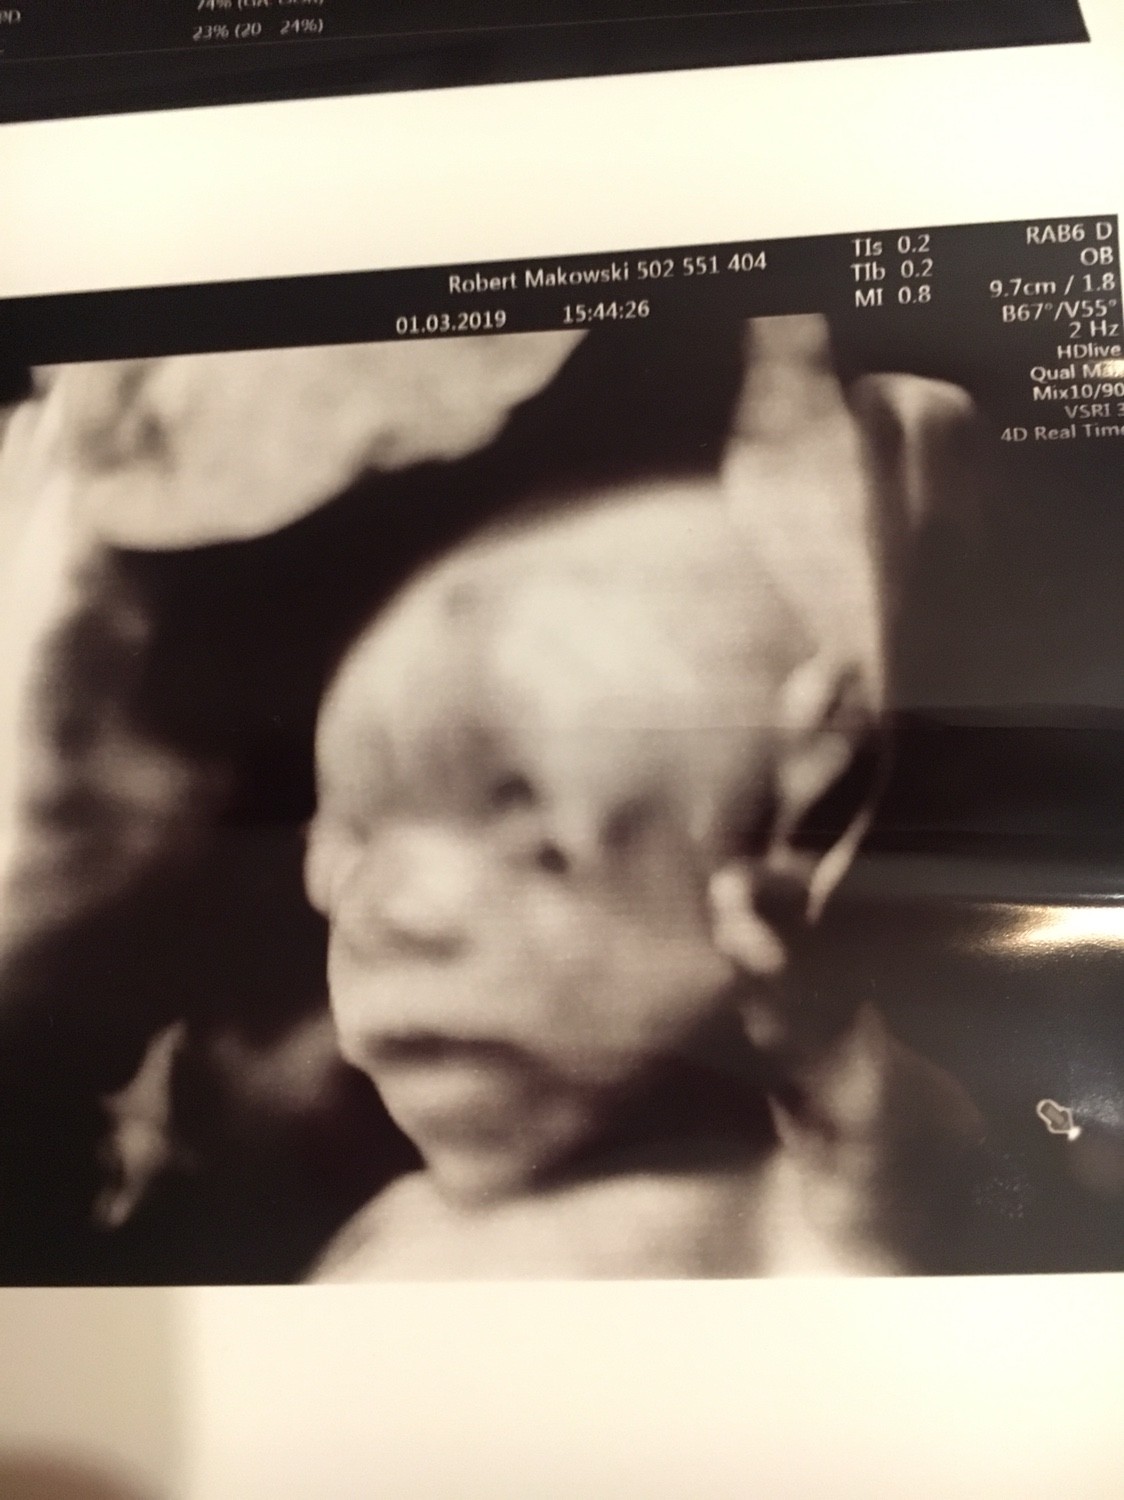

No i ekstra [emoji4] gratulacje.No i połówkowe mamy za sobą

Na 100% córka i to "kawał baby " 420 g

Reszta w załączniku Zobacz załącznik 942392